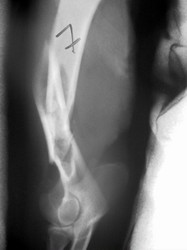

PRÁCTICAS CURSO DE FIJACIÓN EXTERNA PERFECCIONAMIENTO.

Húmero.